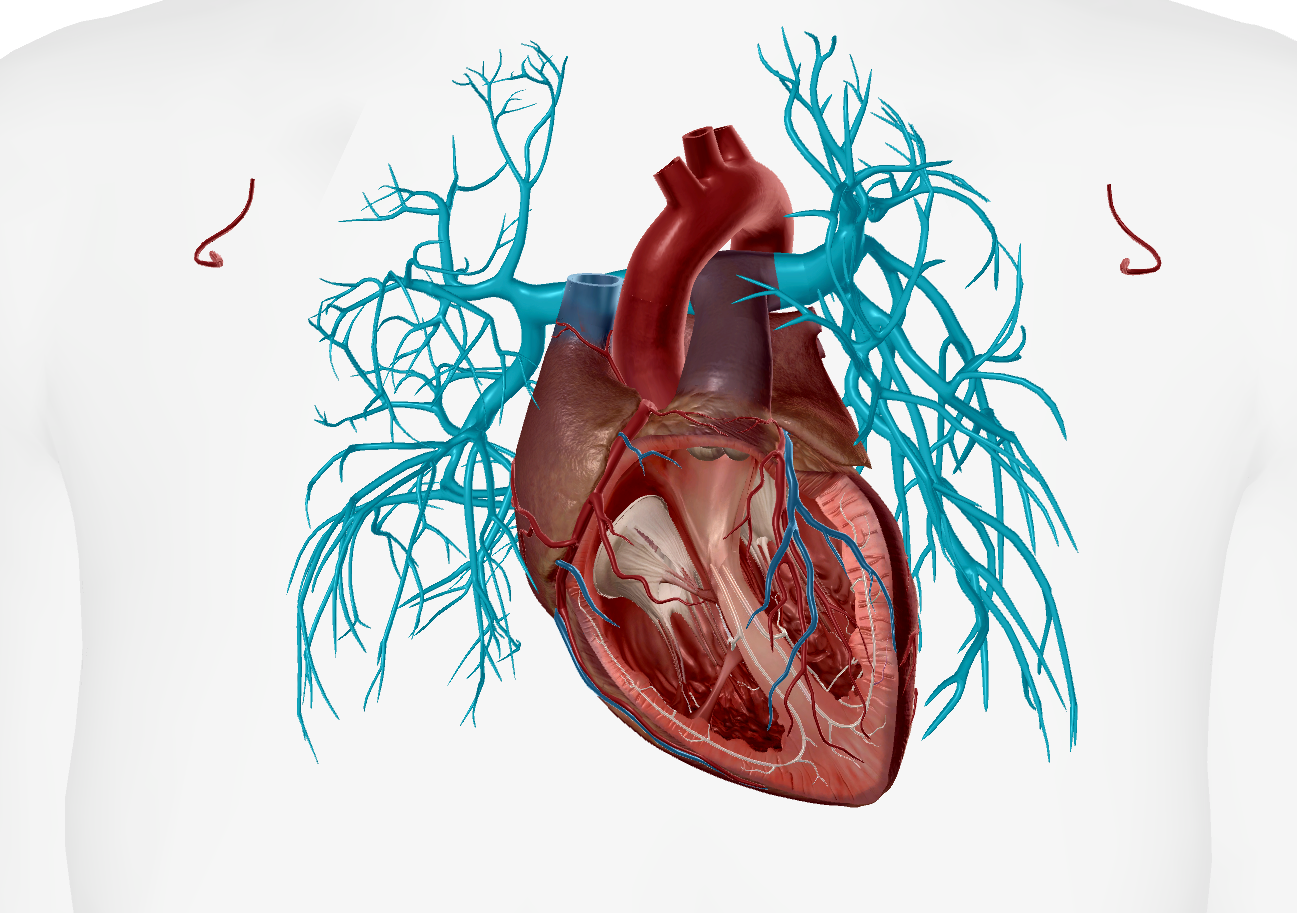

Inferior Vena Cava

Superior Vena Cava

Pulmonary Trunk

Subclavian Artery

Axillary Vein

Subclavian Vein

Anterior Interventricular Artery

Circumflex Branch

Coronary Artery

Middle Cardiac Vein

Aortic Arch

Brachiocephalic Trunk

Thoracic Aorta

Coronary Sinus

Coronary Veins

Great Cardiac Vein

Pulmonary Artery

Pulmonary Vein